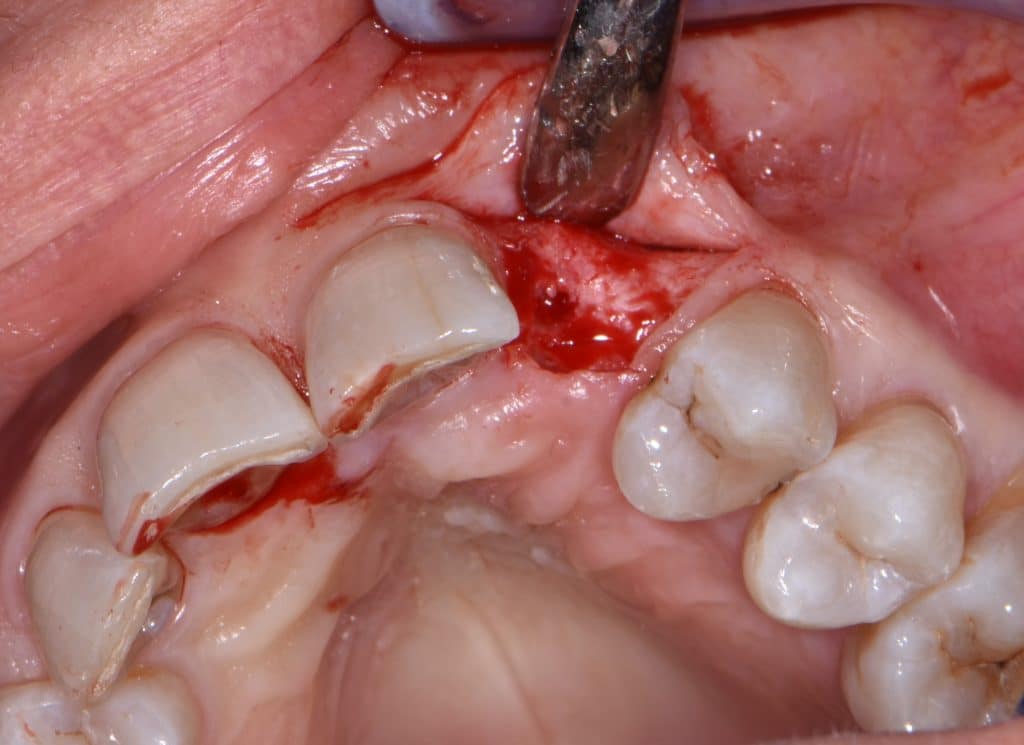

La pz N.G. di anni 52 (ASA 1) viene visitata nel mese di settembre 2017 per la mobilità ed inestetismo dell’elemento protesico 22, (foto iniziali sequenza 1) si evidenzia una frattura parziale della radice, si decide per l’estrazione ( foto sequenza 2) e sostituzione dell’elemento con un restauro implanto-protesico. Purtroppo la scarsa quota ossea apicale all’alveolo post-estrattivo (foto 2 rx) e l’alta valenza estetica dell’elemento ci rende cauti e si programma una socket preservation post estrattiva con l’ausilio delle membrane di prf (foto prf e socket sequenza 3 e 4). Durente i 5 mesi di guarigione la pz porta una protesi parziale mobile (foto 5,2) , a guarigione del sito post estrattivo si evidenzia una buona conservazione dei volumi osseo-gengivali,(foto guarigione sequenza 6) se pur presente una recessione distale all’elemnto 21.Nel mese di febbraio 2018 si procede all’inserimento di un impianto max-stability 3,75x12mm disegnando un lembo anticipato palatino per consentire un aumento dei tessuti vestibolari suturando con tecnica rool flap e trasformando l’elemento parziale mobile in una corona singola a carico immediato sul moncone temporameo applicando i concetti protesici bopt , (foto impianto moncone protesi provvisoria sequenza foto 7-8-9). Durante il periodo di maturazione dei tessuti molli vengono apportate opportune modifiche ai profili del provvisorio al fine di dare maggior spazio al tessuto gengivale, ( fotosequenza 10).Dopo circa 2 mesi dal protesizzazione provvisoria si è proceduto alla realizzazione del manufatto protesico con tecnica chair side sirona con l’ausilio del t-base (foto sequenza 11-12-13), realizzando in una sola seduta una corona in disilicato, ottenendo un risultato più che soddisfacente (Foto 14). Nel controllo a 3 mesi dal carico definitivo si apprezza la perfetta conservazione dei livelli ossei e gengivali. (foto sequenza 15).concludo con un follow up a 18 . Tengo a sottolineare che un caso come questo è stato conducibile con buoni risultati solo grazie alla piena fiducia della pz e alla sua massima motivazione e collaborazione. Ad oggi la pz sorride soddisfatta del risultato. E questo rappresenta la massima ricompensa di chi dedica tutto se stesso alla professione.